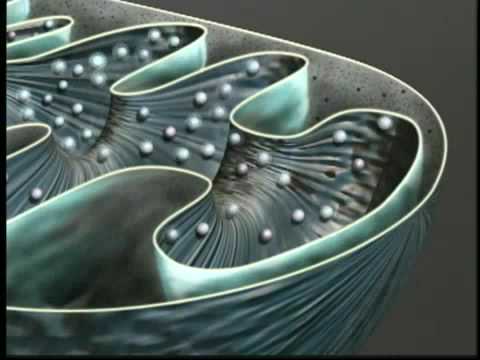

autism mitochondria

Coupling of Mitochondrial Import and Export Translocases by Receptor-Mediated Supercomplex Formation

Nikolaus Pfanner and colleagues explain the import and folding of β-barrel proteins in the mitochon [...]

Mitochondria ATP and cellular respirtaion synthesis. Video streamed by www.AllthingsScience.com All [...]